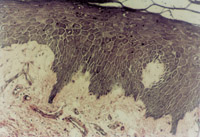

伤后12h急诊入院,检查双下肢为浅Ⅲ度烧伤。创面表皮已坏死剥脱,真皮层变性坏死呈蜡黄色和蜡白色相间(图5-3-1)。取局部组织做病理切片检查,显示上皮组织全层坏死,真皮层胶原纤维变性,结构紊乱,微循环瘀滞(图5-3-2)。

5-3-1 李某 女 20岁,汽油烧伤35%TBSA (深Ⅱ°深型15%,浅Ⅲ°20%)